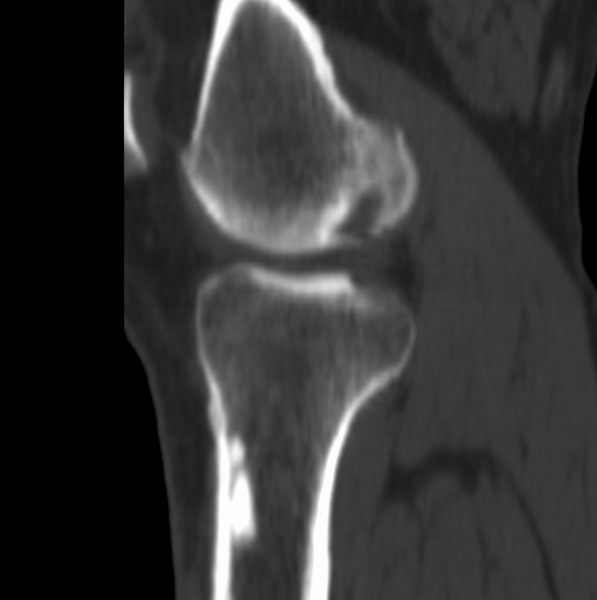

右侧膝关节疼痛一月

男、48

股骨下段、胫骨上段。

1、股骨干骺端病变考虑干骺端纤维性皮质缺损愈后(非骨化性纤维瘤)改变,胫骨近端内生骨瘤(或干骺端纤维性皮质缺损愈后改变);

2、骨关节炎,骨质增生,股骨外侧髁退变性囊肿(关节面软骨下囊肿);

1、股骨干骺端病变考虑干骺端纤维性皮质缺损愈后(非骨化性纤维瘤)改变,胫骨近端内生骨瘤;